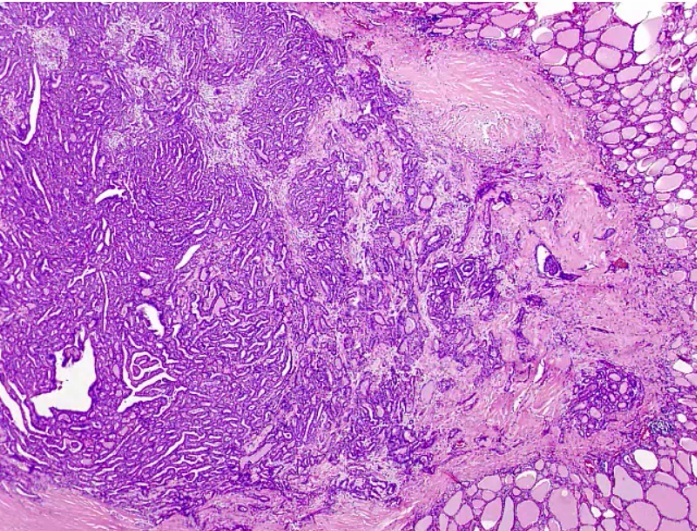

Riedel Thyoiditis

_Occurs when fibrous tissue (collagen) replaces thyroid parenchyma, causing the patient to be hypothyroid.

.,Riedel Thyroiditis. Note how the thyroid gland parenchyma has been overrun by fibrous tissue.

_The thyroid gland is:

Fixed

'Hard as wood' or 'rock-like'

Painless

Often extends beyond the thyroid:

parathyroid gland: hypoparathyroidism

recurrent laryngeal nerves: hoarseness

trachea compression: difficulty breathing.,

_Classified as an IgG4-related systemic disease, which is characterized by:

Lymphoplasmacytic tissue infiltrates with abundant IgG4-producing plasma cells

Storiform fibrosis

Elevated serum IgG4 concentrations.,

_Fibrosis extends beyond the thyroid capsule and into the surrounding tissue in both Riedel thyroiditis and anaplastic carcinoma. A patient with Riedel thyroiditis will be younger (average age 40) than a patient with anaplastic carcinoma, and malignant cells will be absent on biopsy..